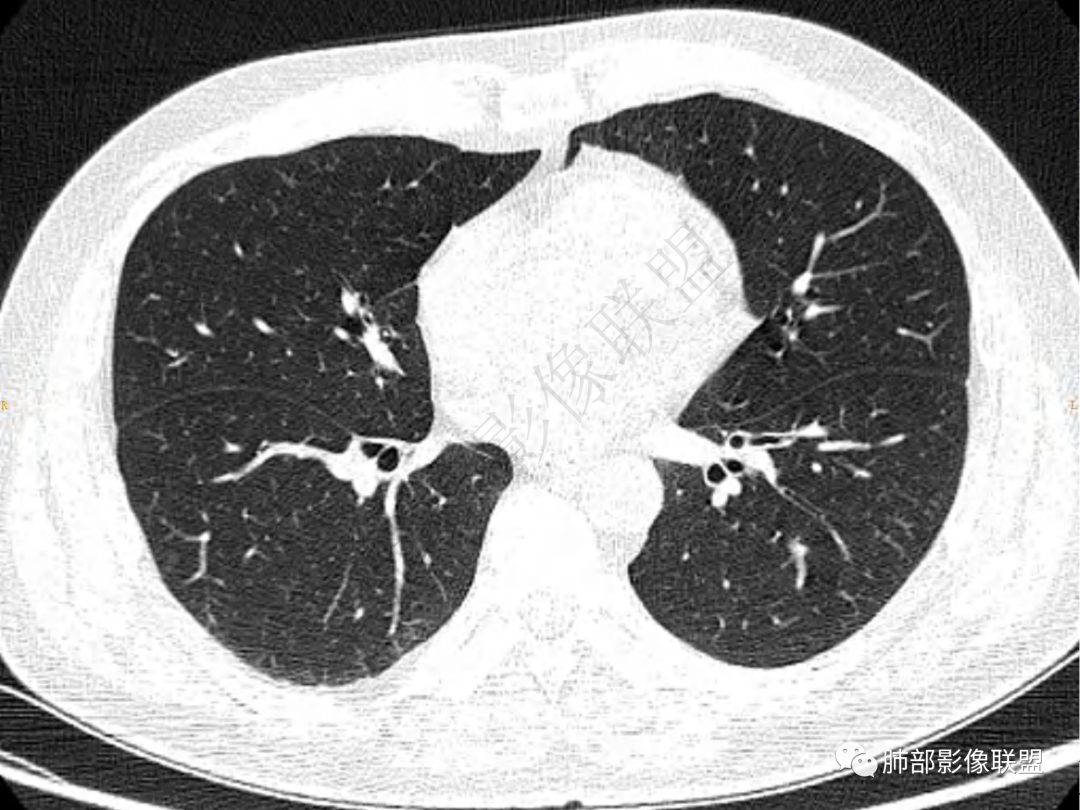

1.中年男性,咳嗽咳痰20余天,间断咯血2周

2.左肺下叶团片影,跨背段及内前基底段,实性部分类椭圆形,密度不甚均匀,可见毛刺及棘状突起,未见典型分叶及胸膜凹陷。病灶上下缘可见相应肺段支气管旁进侧出,管壁轻度增厚,未见狭窄阻塞。

3.周边较大范围磨玻璃影,边界相当模糊,小叶增厚明显。注意叶裂另一侧、左肺舌段亦可见磨玻璃影及增厚的小叶间隔。未见明确卫星病灶。